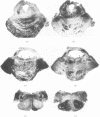

A case is reported of a 52 year old man who sustained a head injury and survived for three years and two months in coma. He was subsequently shown to have severe brain stem damage, with a bilateral lesion of the central tegmental tract and bilateral hypertrophic olivary degeneration, associated with a widespread loss of Purkinje cells in the cerebellar cortex. Hypertrophic olivary degeneration is considered to be a trans-synaptic change associated with a lesion of the central tegmental tract, which in this case was thought to be due to primary shearing injury of the brain stem involving the superior cerebellar peduncles. It is suggested that, as a consequence of long survival, Purkinje cell degeneration represents further trans-synaptic changes, the result of neuronal degeneration in the hypertrophied inferior olivary nuclei and in the dentate nuclei. A chain or `circuit' of degenerated neurones is thereby produced.